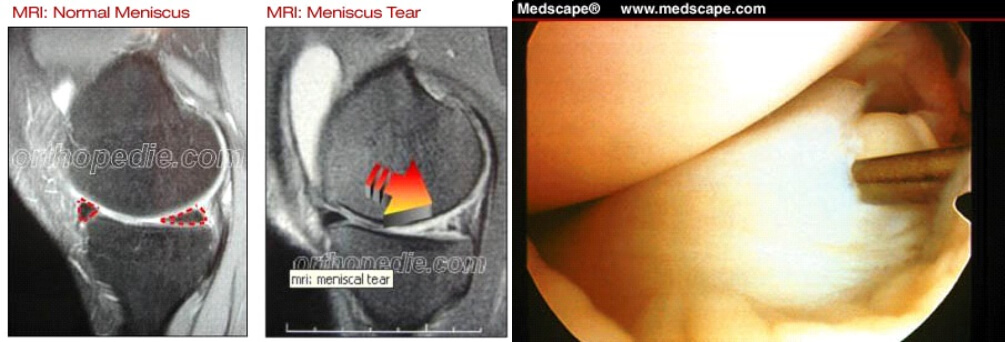

Meniscus letsels

Kunnen ontstaan door een ongeval (posttraumatisch) of door slijtage (degeneratief)

Gezien de functie van de meniscus (optimalisatie van de gewichtsverdeling tussen het boven en het onderbeen) is het impact van deze letsels ( zeker bij jonge patiënten) niet te onderschatten daar deze letsels kunnen leiden tot vervroegde slijtage van het kraakbeen (artrose)

De behandeling van dergelijke letsels is, afhankelijk ook van het type letsel en de leeftijd van patiënt, zo behoudend (conservatief) mogelijk en kan bestaan uit een arthroscopische(via kijkoperatie)

meniscushechting

Zo beperkt mogelijke (partiële) meniscus resectie.

Meniscus transplantatie in specifieke gevallen.